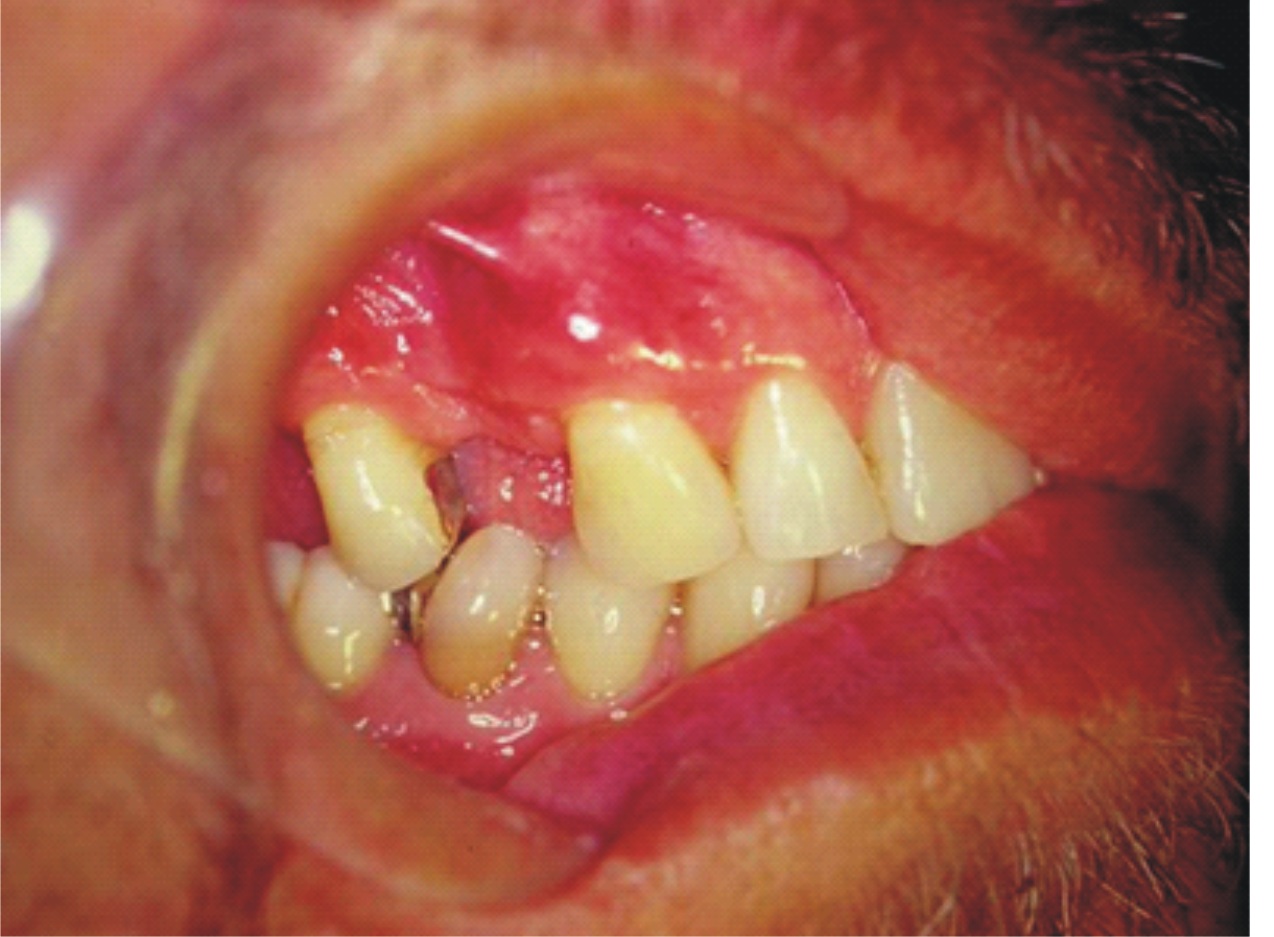

- Figura 1A (Português (Brasil))

- Figura 1B (Português (Brasil))

- Figura 1C (Português (Brasil))